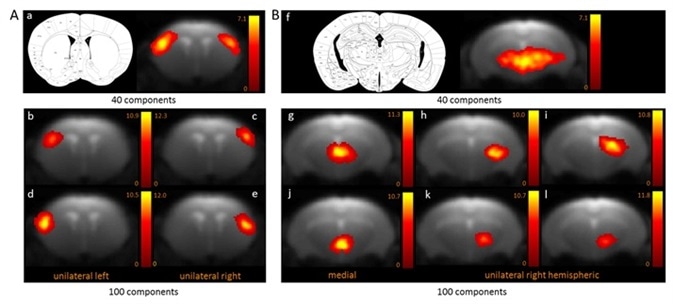

Two functional areas related to cortical (Figure 1A) and subcortical (Figure 1B) networks detected with 100-ICASSO and 40-ICASSO were comparatively presented. The cortical resting-state cluster, located at the primary somatosensory cortex (SSC) that is anatomically well-defined; secondary somatosensory cortex; and barrel field is all representative of the bi-hemispherical or bilateral connectivity pattern acquired with 40-ICASSO, as shown in Figure 1 A-a.

Refining the analysis with 100-ICASSO, as shown in Figures 1 A-b to e, led to the segregation of the functional areas of somatosensory cortex. Unilateral connectivity patterns were unraveled, which suggests that the SSC may have different low frequency variations of the BOLD signal in both hemispheres. Therefore, when 100-ICASSO is used, resting-state networks differentiated in single components from 40-ICASSO were divided into many functional circuits.

In addition to being relevant for cortical areas, this was also a common feature of subcortical regions. Shown in Figure 1B is the division of the thalamic networks, from a single component acquired with 40-ICASSO (Figures 1 B-f), into 6 functional clusters produced with 100-ICASSO.

BOLD resting-state fMRI based cortical (A) and thalamic (B) mouse brain functional connectivity clusters, comparatively revealed by 40- (a, f) and 100-ICASSO (b–e and g–l). All images represent spatial color-coded z-maps of the independent components.

Figure 1. BOLD resting-state fMRI based cortical (A) and thalamic (B) mouse brain functional connectivity clusters, comparatively revealed by 40- (a, f) and 100-ICASSO (b–e and g–l). All images represent spatial color-coded z-maps of the independent components. Image Credit: Bruker BioSpin Group